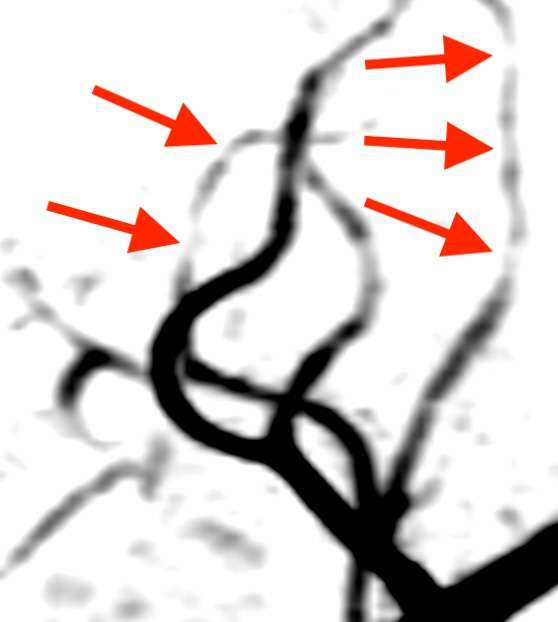

頭部MRA検査では、中大脳動脈という血管が所々細くなっていました。

こうした画像所見から、可逆性脳血管攣縮症候群と診断しました。この疾患では、様々な場所の脳血管が縮んで細くなる多発性分節性狭窄1)という特徴があります。また、進行とともに血管の先端部から中心部に攣縮が移動する求心性移行2)という経過をとる事などから、頭痛の場所が移動する事があります。